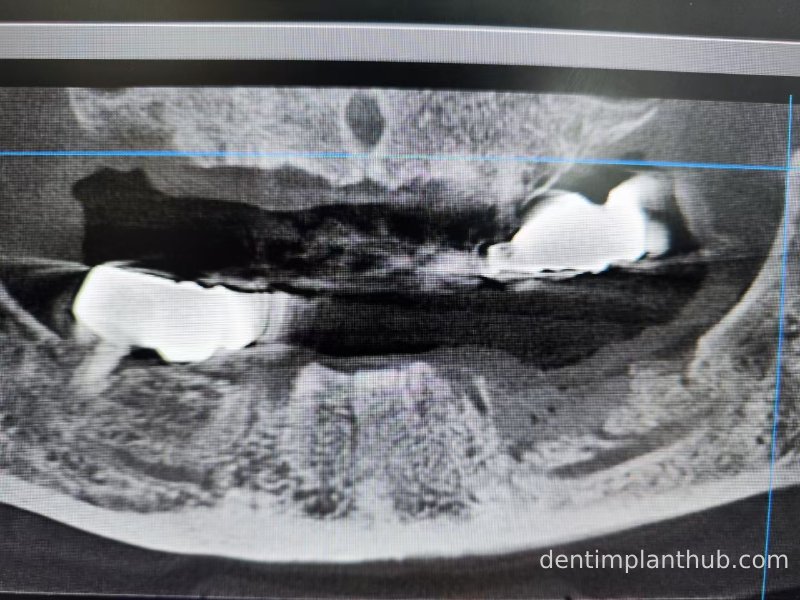

CBCT review results on 13 May '24

46

44

42

32

34

36

Maxillary condition as shown by CBCT on 13/5/24